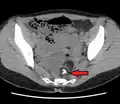

A complex cyst due to a dermoid as seen on CT. Arrow points to bone or teeth.